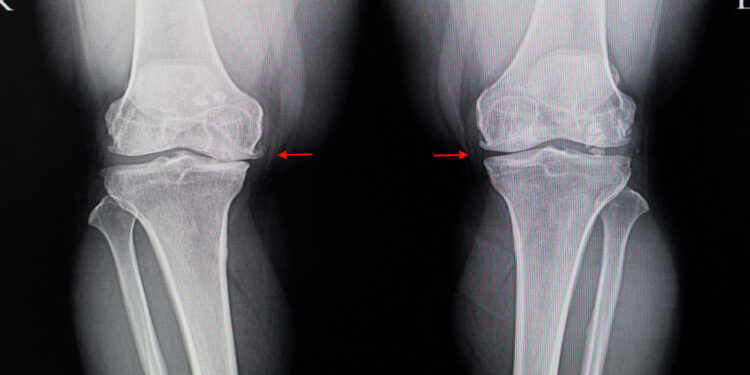

(MedPage Today) — Hopes that the plant extract known as diacerein could relieve pain and disability from osteoarthritis (OA) of the knee now seem forlorn in the wake of an Australian trial that failed to find any benefit.